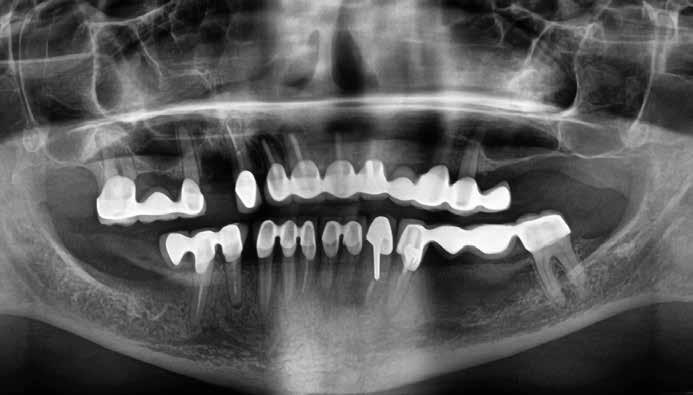

A műtéti tervezéshez mindkét esetben CBCT-felvételt használtunk, majd az utánkövetési időszakban periapikális röntgenfelvételekkel ellenőriztük az implantátumokat. A fogeltávolítást követően azonnali implantáció történt, az alveolus fala és az implantátum felszíne közt fennmaradó réseket csontpótlóval töltöttük ki. A három hónapos gyógyulás leteltével az ideiglenes koronákat eltávolítottuk, A-szilikonnal lenyomatot vettünk, majd három lítium-diszilikát és egy monolitikus cirkónium-dioxid korona készült. A páciensek utánkövetése mindkét esetben minimum tizenkét hónap volt, amelynek során valamennyi implantátumot klinikailag és radiológiailag is sikeresnek ítéltünk az osszeointegráció, a marginális csont stabilitása és a periimplantáris szövetek egészsége tekintetében.

1. a–d. ábrák: Kiindulási klinikai állapot a két páciens esetében: Az első páciensnél a jobb felső premolárisok és az első moláris, a második páciensnél a bal felső második premoláris.

heléssel vagy anélkül). Az első páciensnél gyökérreszorpció miatt szükségessé vált a jobb felső premolárisok és az első moláris eltávolítása (1. a–b ábrák). A második páciensnél a bal felső második premoláris frakturát szenvedett (1. c–d ábrák) Az átfogó tervezést és diagnosztikát CBCT-felvétel segítségével végeztük (2. a–c ábrák), a posztoperatív kontroll és az utánkövetés időszakában pedig periapikális röntgenfelvételeket készítettünk. A jelen tanulmányban résztvevő valamennyi páciens nemdohányzó volt, jó, vagy gyógyszeresen jól karbantartott általános egészségi állapotnak örvendett. A hatékony plakk-kontroll ellenére műtét előtt mindkét páciensnél végeztünk supragingivális depurálást és gyökérsimítást.

2. a–c ábrák: Kiindulási CBCT-felvételek.

A végleges ragasztást követően röntgenfelvételt készítettünk, amelyet összevetettünk a közvetlenül a műtét után készült felvételekkel: a marginális csontszint változatlan volt. A pácienseket 14 hónapon keresztül rendszeresen visszahívtuk. Klinikai és röntgenvizsgálattal sem tapasztaltunk komplikációt (12. a–b ábrák)

10. a ábra: Végleges lítium-diszilikát koronák. – 10. b ábra: Végleges monolitikus cirkónium-dioxid korona. – 11. a–b ábrák: Klinikai megjelenés tizenkét hónap elteltével. 12. a–b ábrák: Tizenkét hónapos kontrollröntgen-felvételek.